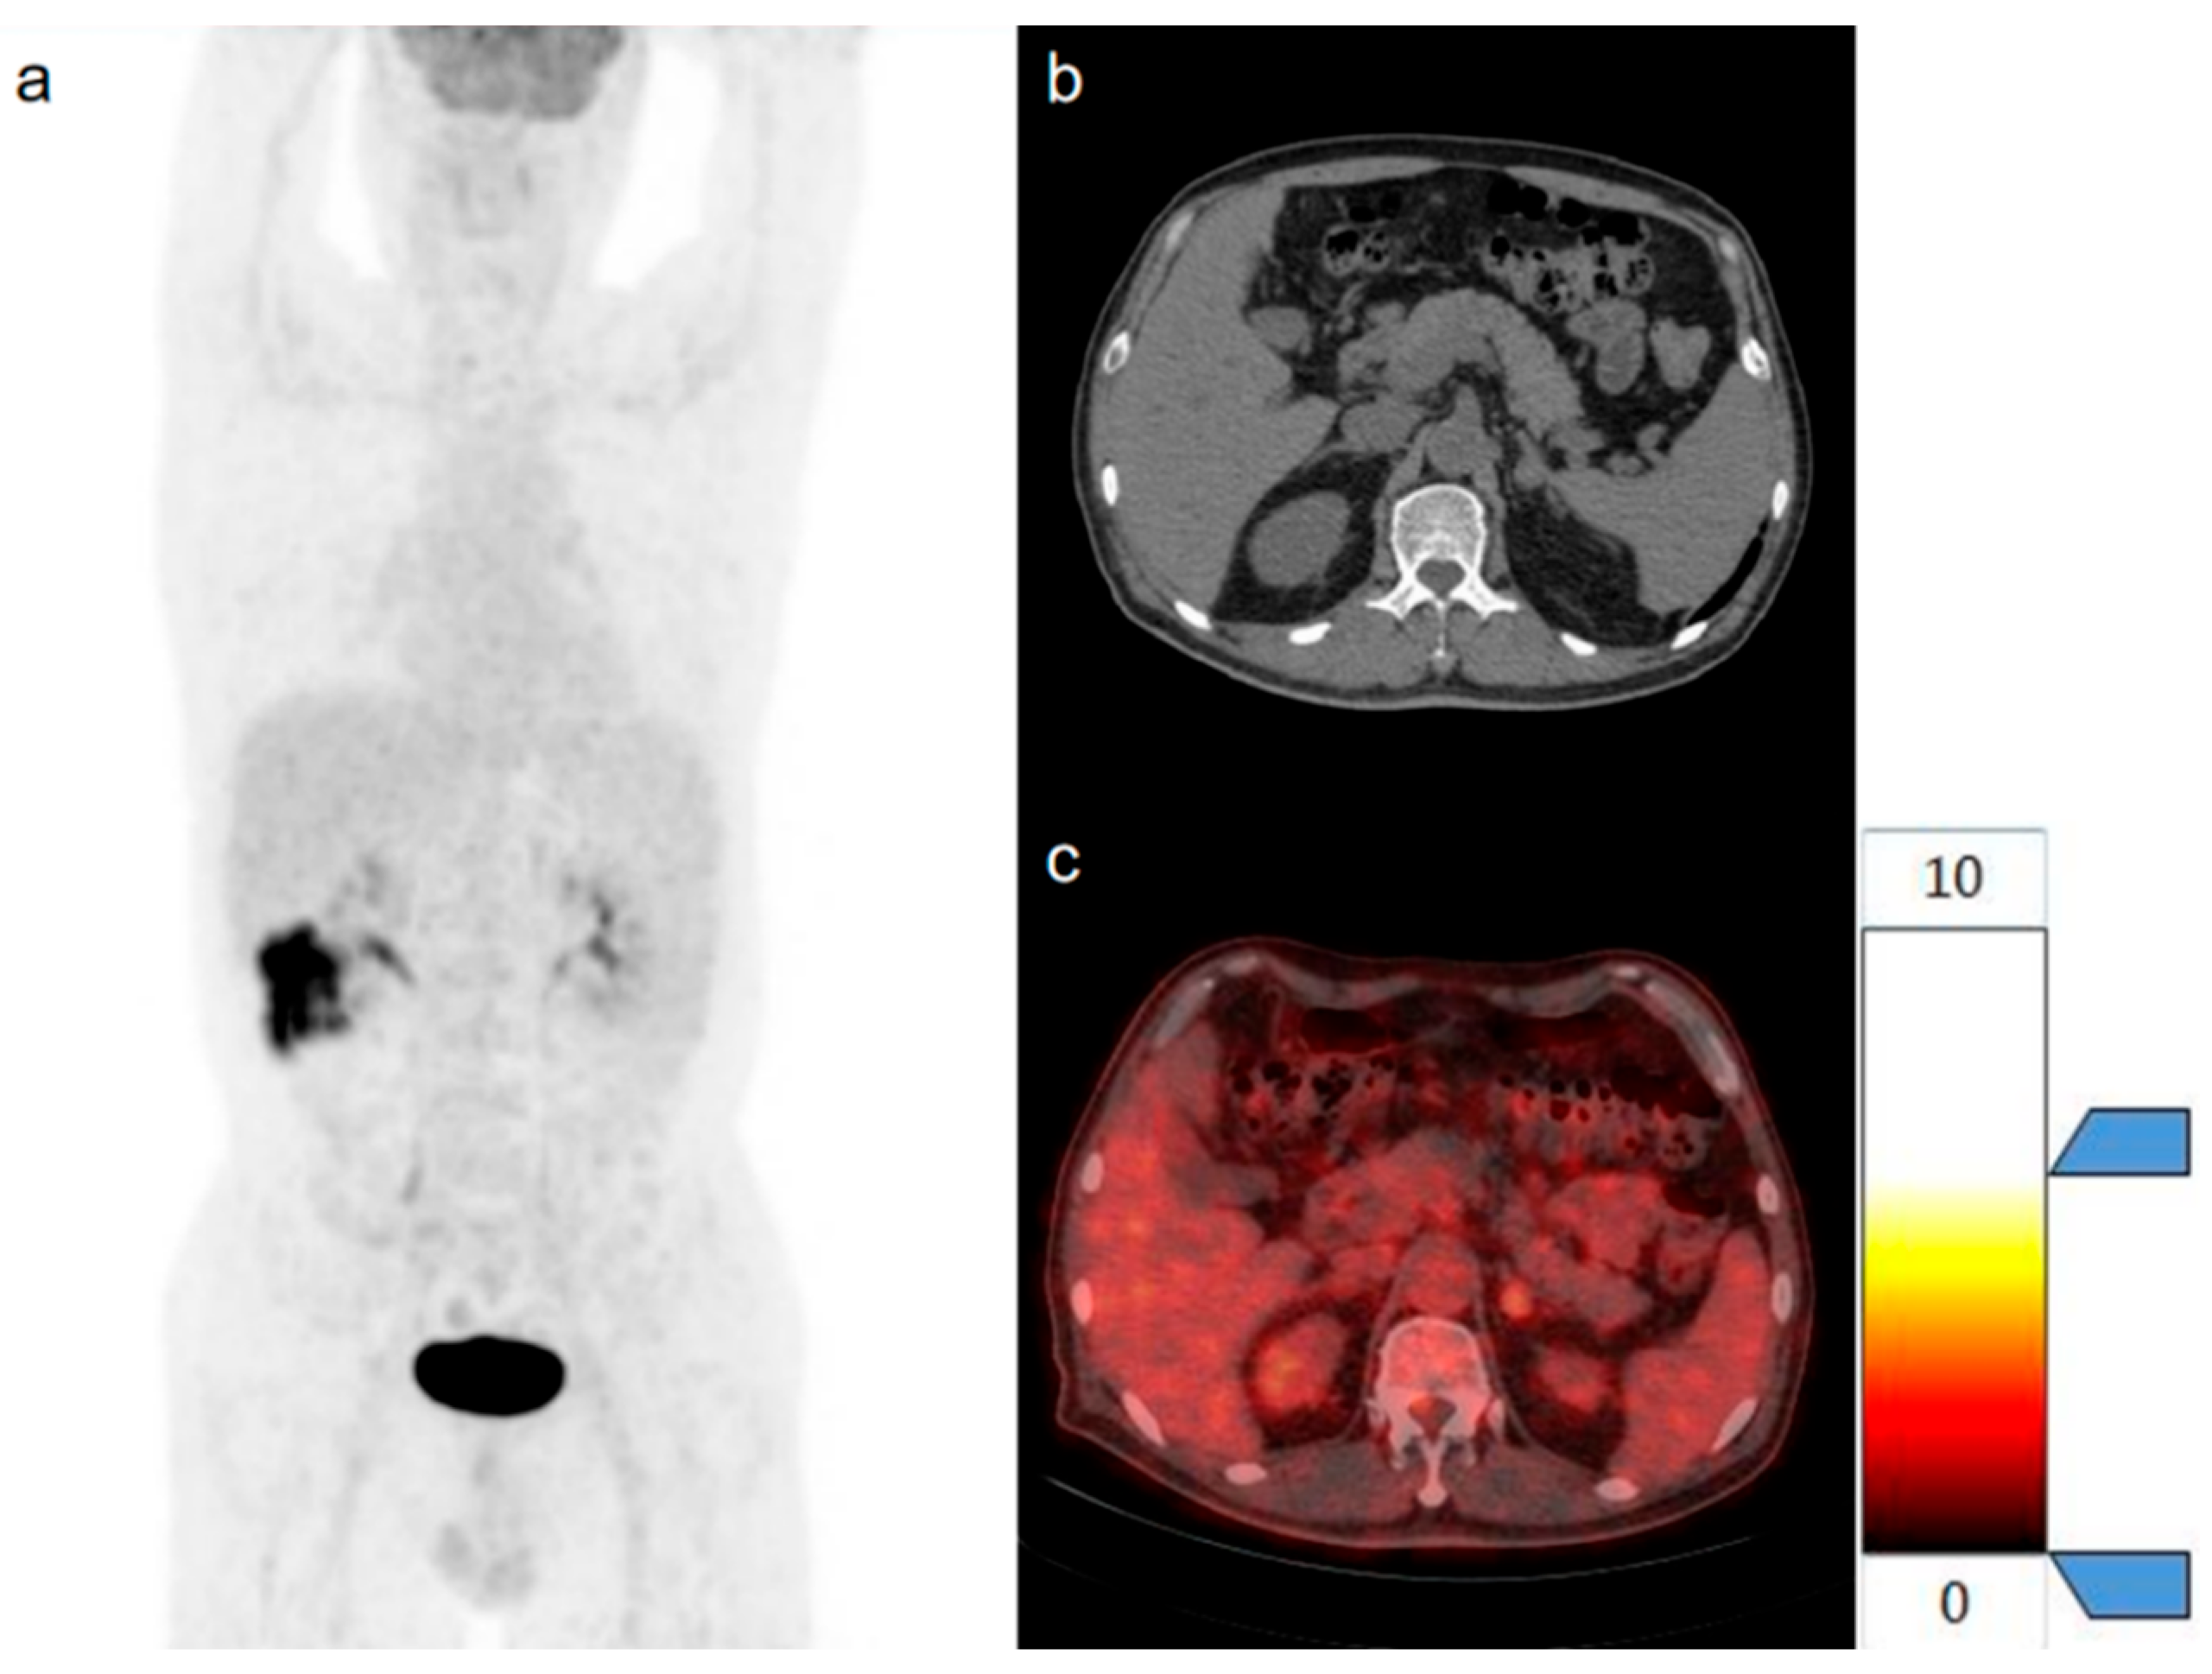

2.5. Three-Dimensional Segmentation